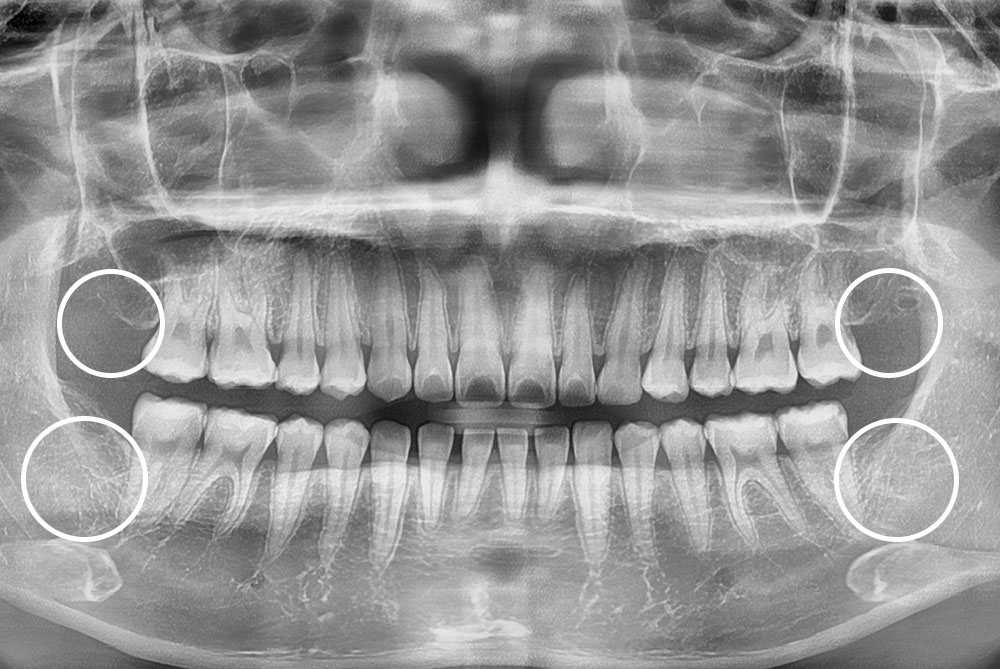

[사랑니] 매복 사랑니 발치

치료후 : 2022-10-01

세종치과는 구강악안면외과학 박사이신 원장님이 발치하는 치과입니다.